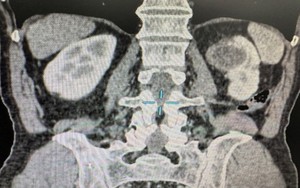

Người đàn ông phát hiện ung thư thận sau khi có dấu hiệu bất thường này suốt 6 tháng

Đau thắt lưng trái hơn 6 tháng, người đàn ông nhập viện phát hiện mắc ung thư thận giai đoạn sớm.